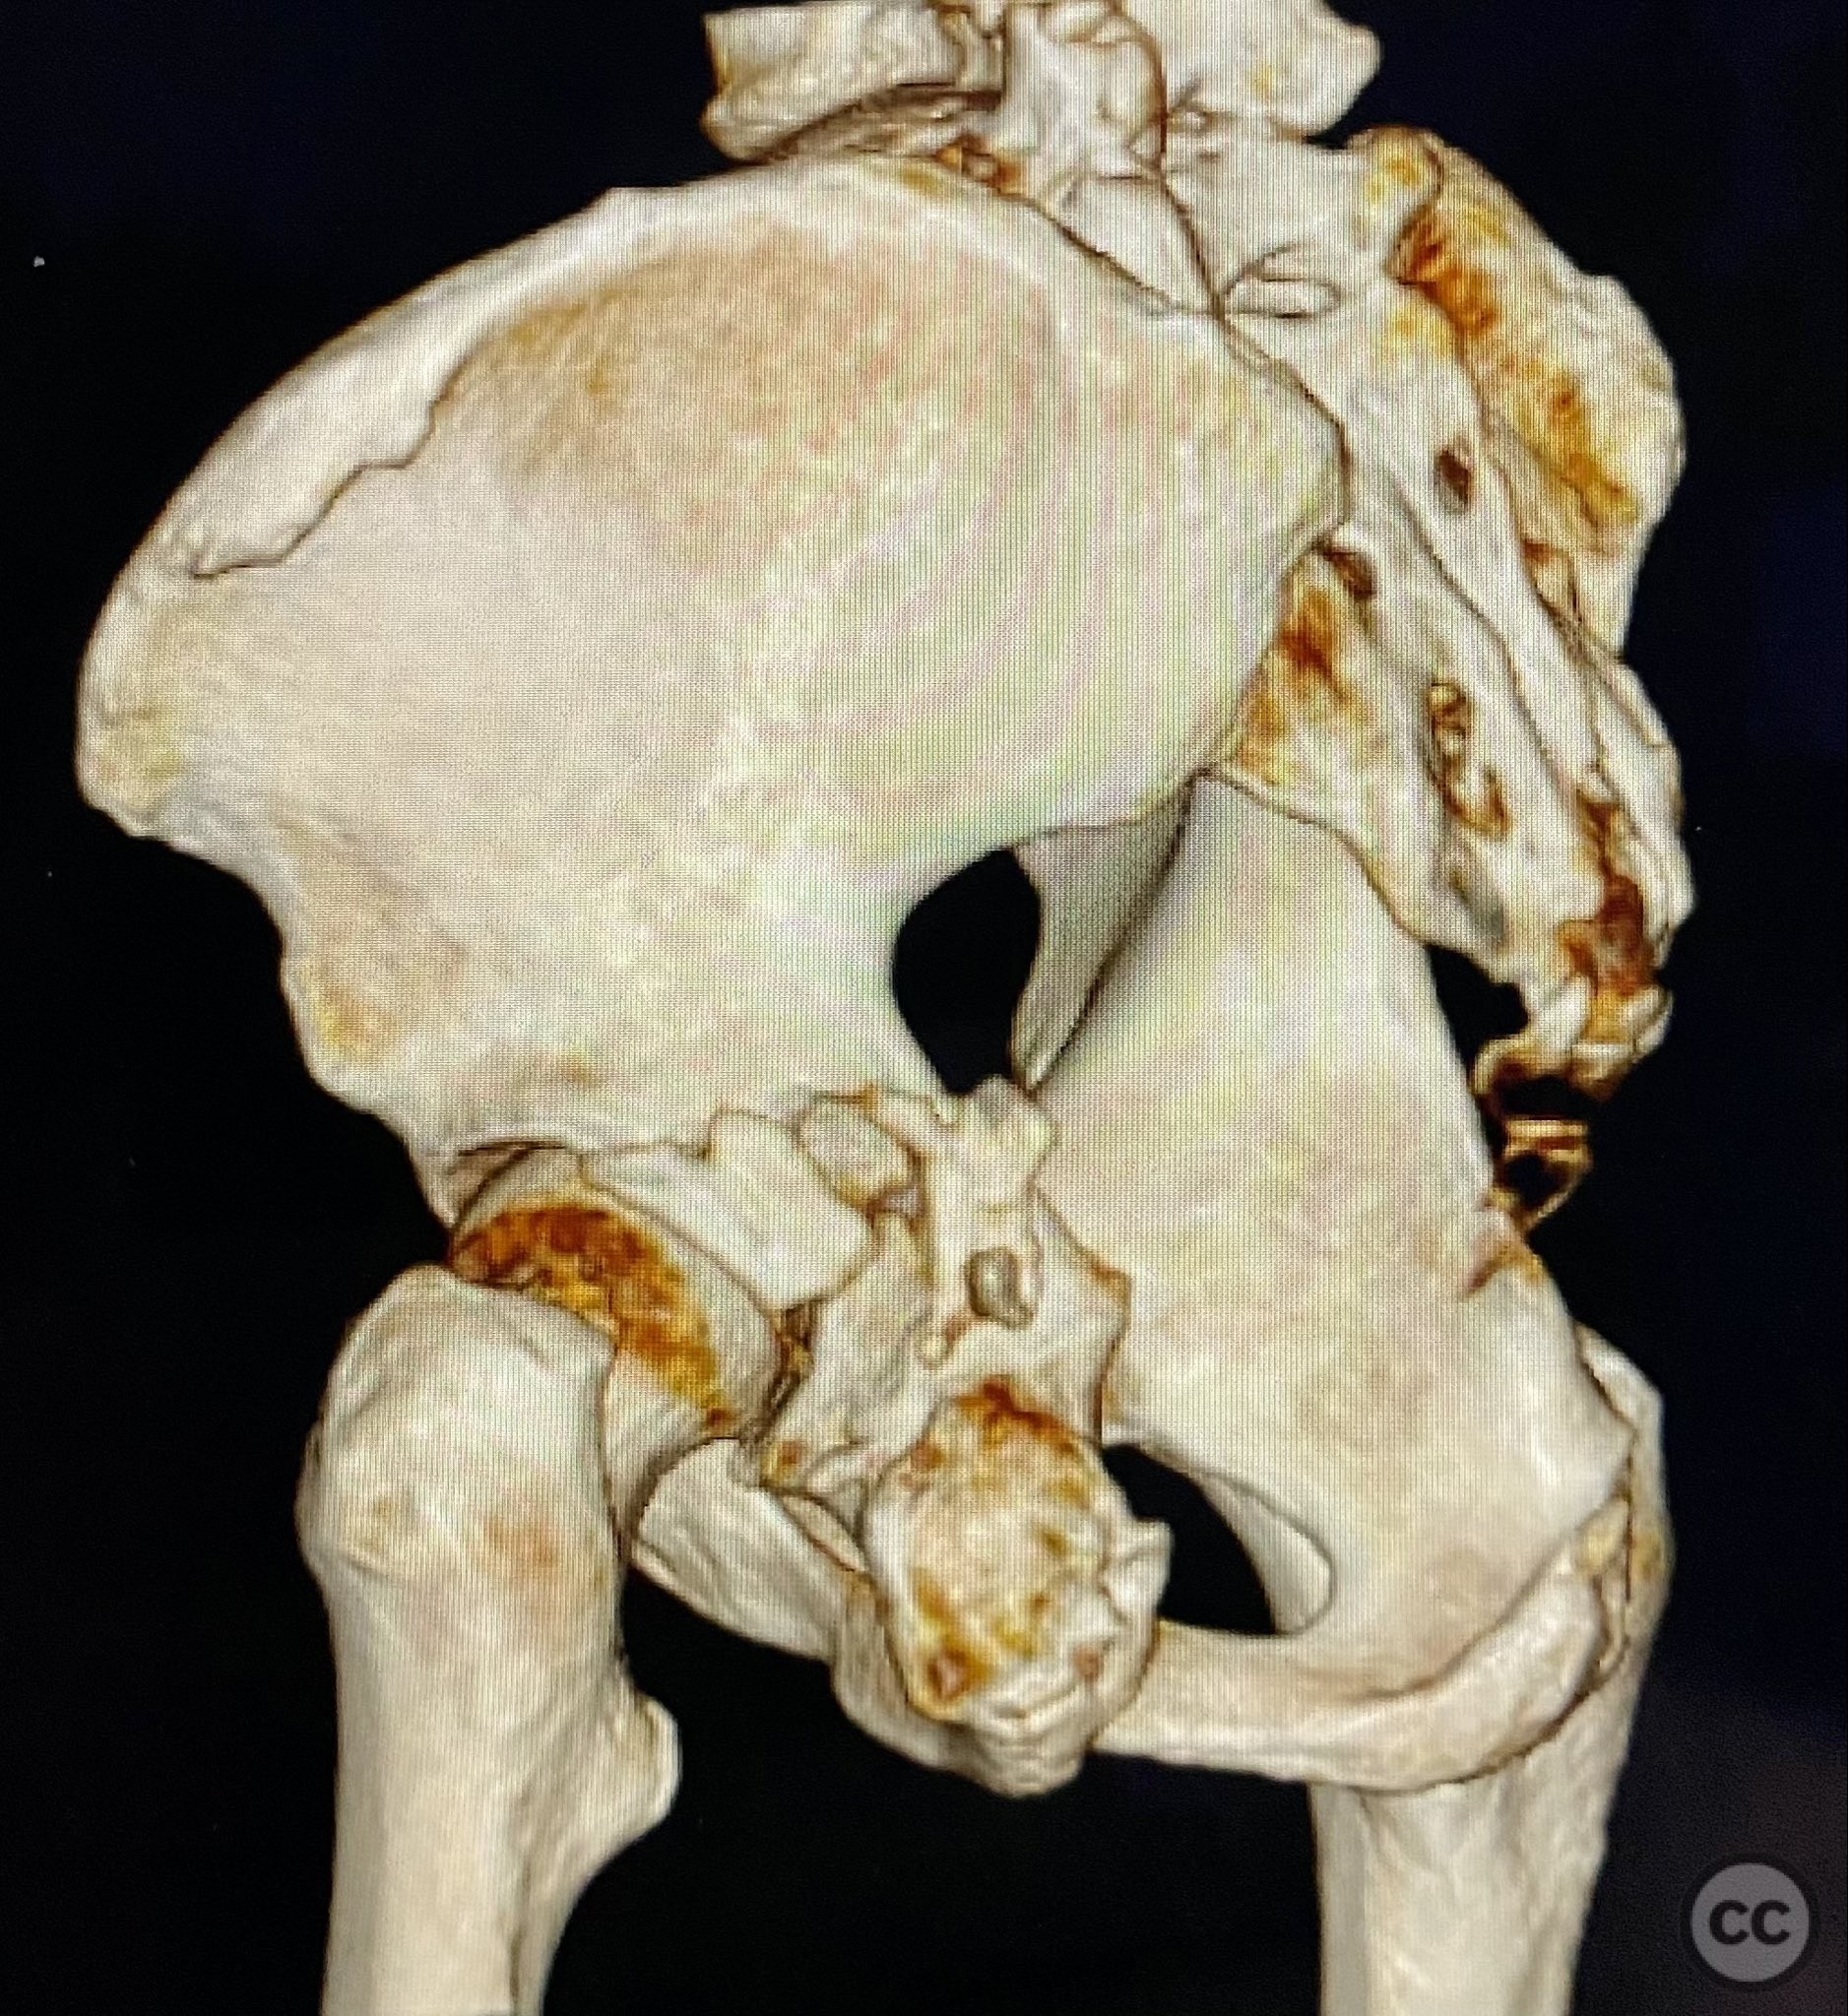

Clinical and radiological findings:  A patient sustained a posterior wall acetabular fracture-dislocation, characterized by comminution of the posterior wall, impaction of fragments into the posterior column region, and intra-articular loose fragments within the fossa acetabuli. Sagittal imaging demonstrated femoral head impalement on the intact wall, raising concern for potential irreducibility. Coronal and axial CT images revealed acetabular and femoral head impactions, peripheral wall comminution, incomplete fracture extension at the acetabular notch and quadrilateral surface, and an articular fragment within the joint. Surface renderings confirmed the extent of peripheral wall comminution and impaction. Despite these findings, a closed manipulative reduction was successfully achieved, resulting in a congruent reduction on post-reduction imaging.